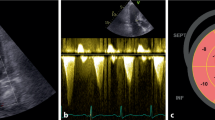

Transthoracic echocardiography

As recommended in the current professional guidelines, additional information from cardiovascular imaging contributes to CTRCD risk stratification at baseline. TTE is the preferred imaging modality for baseline risk stratification because it provides quantitative assessment of LV systolic and diastolic function, significant valve disease, and coronary artery disease by abnormal wall motion. Furthermore, given that decreasing LVEF and LV GLS are the core of CTRCD diagnosis, baseline TTE information serves as a reference for subsequent follow-up studies.

Coronary artery calcium score

Recently, coronary artery calcium score (CACS) acquired by electron beam CT or multidetector CT has been widely used in the asymptomatic general population for cardiovascular risk stratification [29]. There has been an attempt to incorporate CACS into risk stratification for CTRCD in cancer patients and long-term CVD risk assessment in cancer survivors. Given that most cancer patients underwent noncardiac chest CT or radiation therapy (RT) planning CT for staging and treatment planning, CACS by noncardiac CT may be useful for risk stratification and assessment of CV. Recent studies have shown that increased CACS on chest CT or RT planning CT is associated with future CVD risk [30, 31]. Furthermore, it is feasible to fully automate the evaluation of CACS using sophisticated automated algorithms or machine-learning technology [30,31,32,33,34]. However, given that the evidence of future CTRCD and CVD risk assessment with CACS using noncardiac CT has been primarily developed and validated in breast cancer patients with a focus on long-term CVD risk prediction and not CTRCD during cancer therapy, additional evidence for the use of CACS for prediction of CTRCD during anticancer treatment is required.